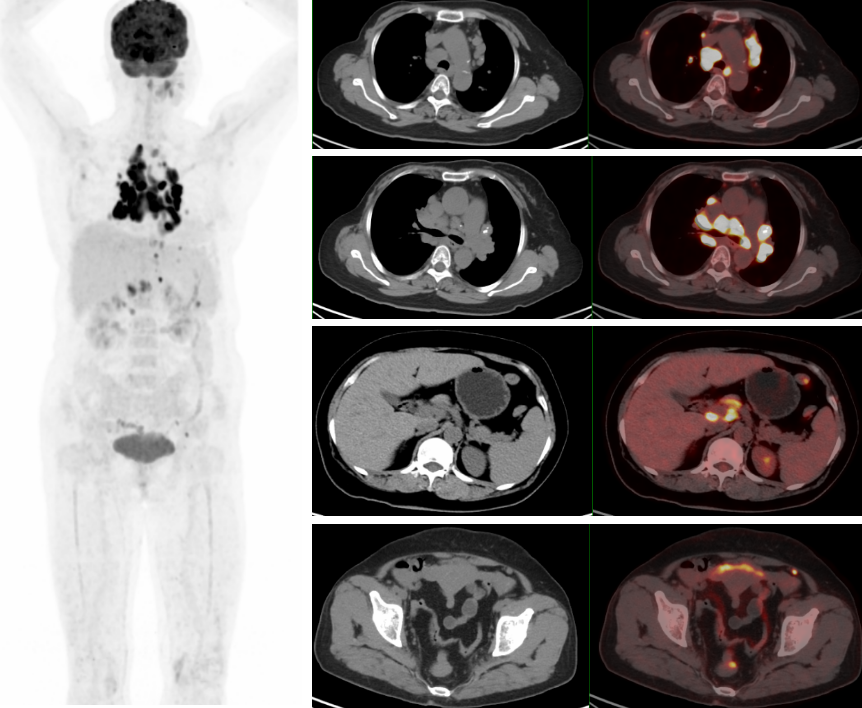

PET/CT示:雙側(cè)鎖骨上、縱隔、胸骨后、雙肺門(mén)、雙側(cè)肋骨旁、腹腔、腹膜后、盆腔及左側(cè)腹股溝見(jiàn)多枚代謝異常增高淋巴結(jié),較大者約3.4×2.1cm,SUVmax約20.7。

PET/CT診斷:考慮結(jié)節(jié)病,建議病理檢查。

18F-FDG PET/CT在腫瘤患者的全身評(píng)估中具有顯著優(yōu)勢(shì),在乳腺癌術(shù)后出現(xiàn)縱隔和肺門(mén)腫大淋巴結(jié)時(shí),不但能顯示淋巴結(jié)全身的分布特征,且能更早發(fā)現(xiàn)胸外病變及隱匿性病變,同時(shí)體現(xiàn)不同部位淋巴結(jié)的FDG攝取程度,判定病灶活動(dòng)性,有利于結(jié)節(jié)病與乳腺癌術(shù)后復(fù)發(fā)或淋巴瘤等的鑒別診斷。由于結(jié)節(jié)病的診斷主要依靠組織病理學(xué)活檢,PET/CT可以提示適合的活檢部位,提高活檢診斷成功率。

此例患者由于乳腺癌的病史,臨床初步懷疑轉(zhuǎn)移。PET/CT顯示縱隔、肺門(mén)淋巴結(jié)腫大,且呈對(duì)稱(chēng)性分布,密度均勻,邊界清晰,無(wú)明顯融合,F(xiàn)DG高攝??;此外可見(jiàn)多發(fā)腹盆部,頸部淋巴結(jié)次之,分布較散,體積及FDG攝取小于縱隔和肺門(mén)淋巴結(jié),也不是乳腺癌術(shù)后易轉(zhuǎn)移的部位。綜上考慮符合結(jié)節(jié)病表現(xiàn),最終得到病理證實(shí),患者因此避免了不必要的抗腫瘤治療。